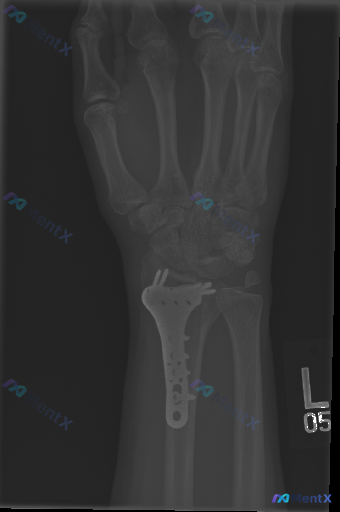

整理到一份左侧桡骨远端骨折术后复查的左侧手腕正位X光资料,分享给大家讨论: 基本背景 左侧桡骨远端骨折切开复位内固定术后,本次为常规复查影像。 影像可见表现 1. 桡骨远端掌侧可见金属接骨板及多枚螺钉,位置与解剖结构基本匹配; 2. 桡骨远端骨折线趋于模糊,存在骨痂形成迹象; 3. 尺骨远端茎突处可...